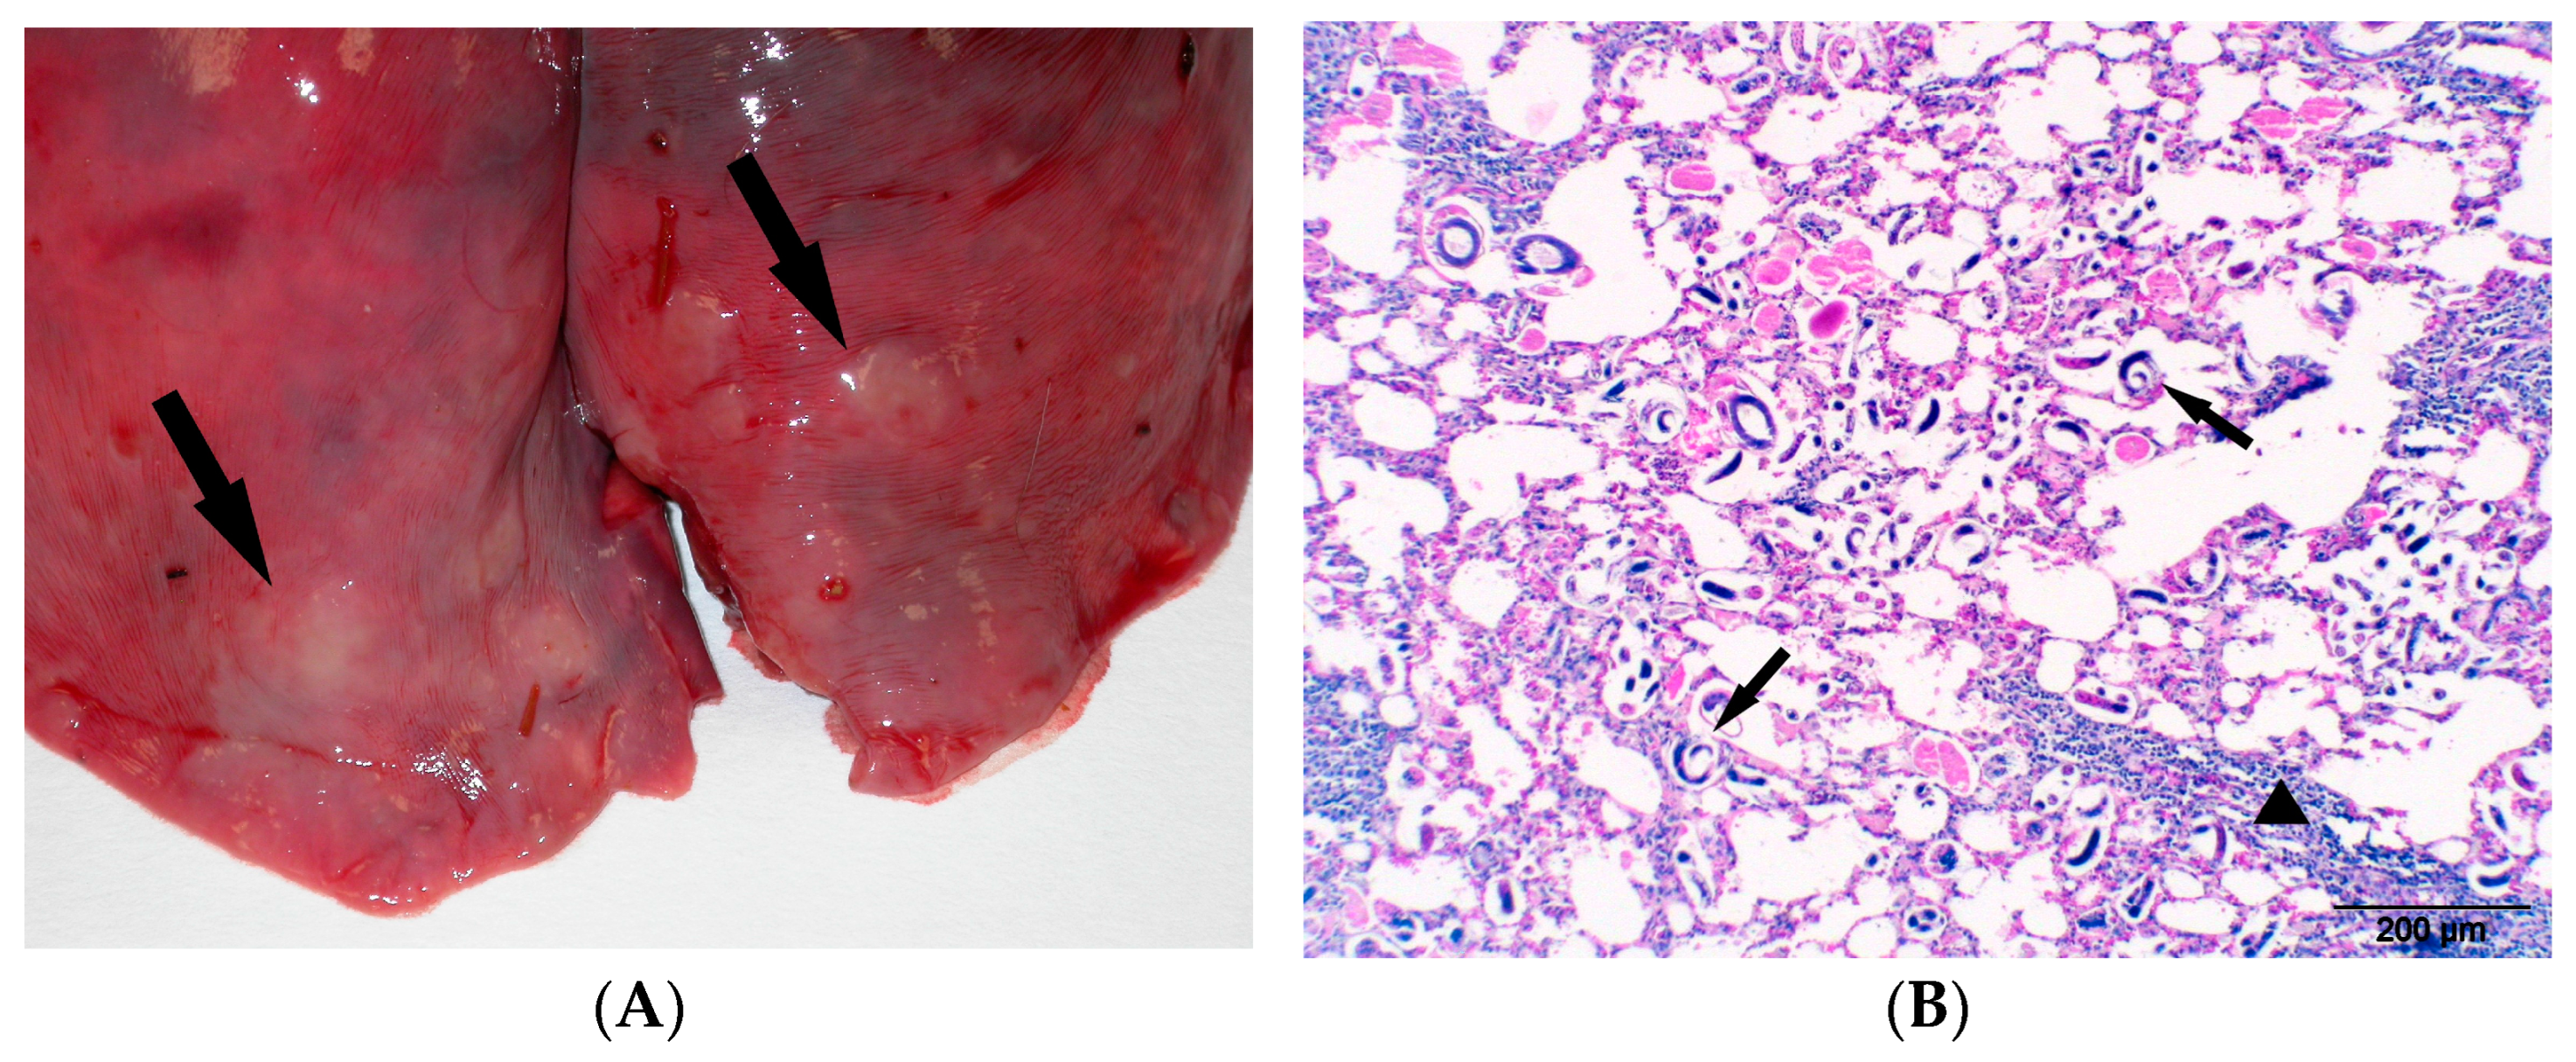

3.2. Gross Lesions and Analytical Results